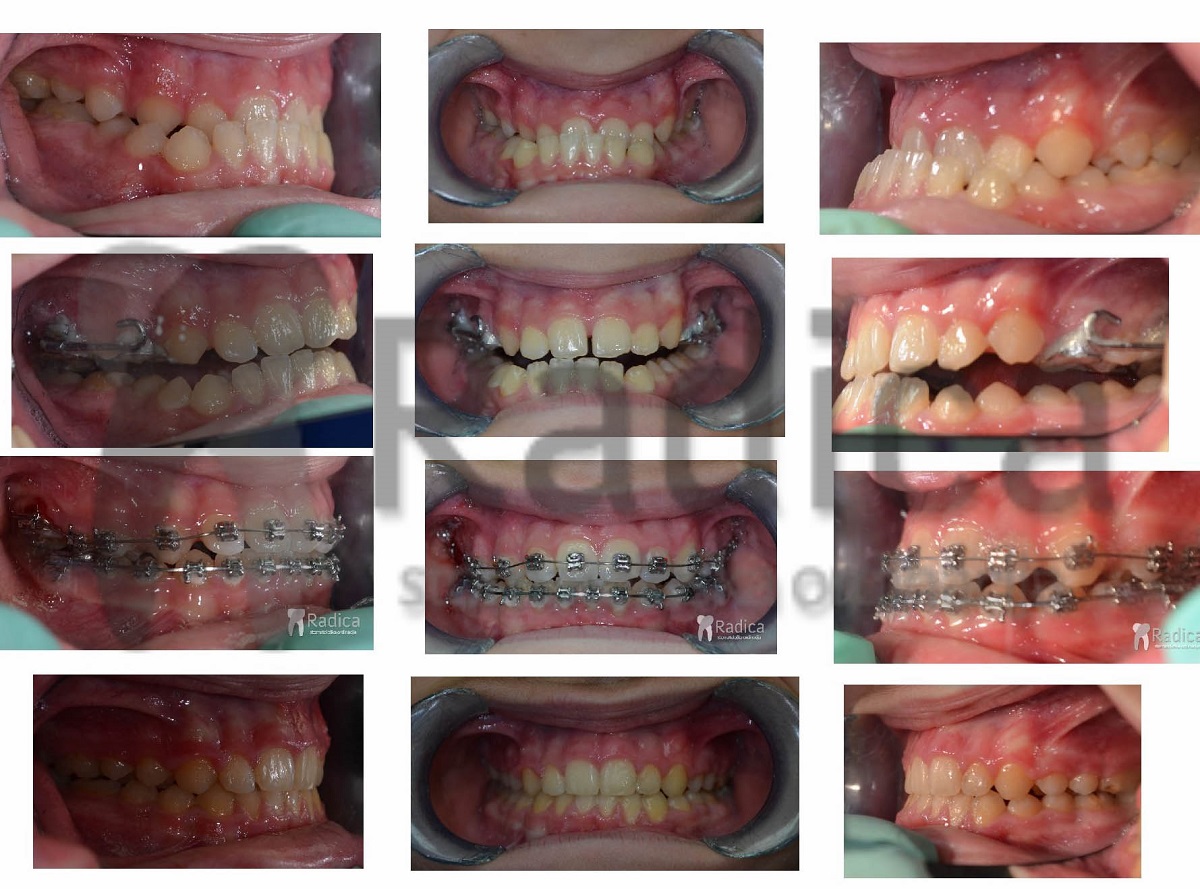

4. primjer – jednostrani rascjep nepca

6. primjer – pseudoprogenija i hypodontia (nedostatak) gornjih trajnih lateralnih sjekutića. Osim hyraxa, pacijent nosi i Delairovu masku za stimulaciju rasta gornje čeljusti.

Slike završetka terapije